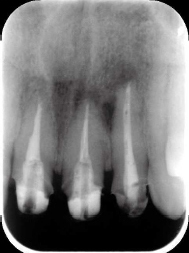

術前X線写真